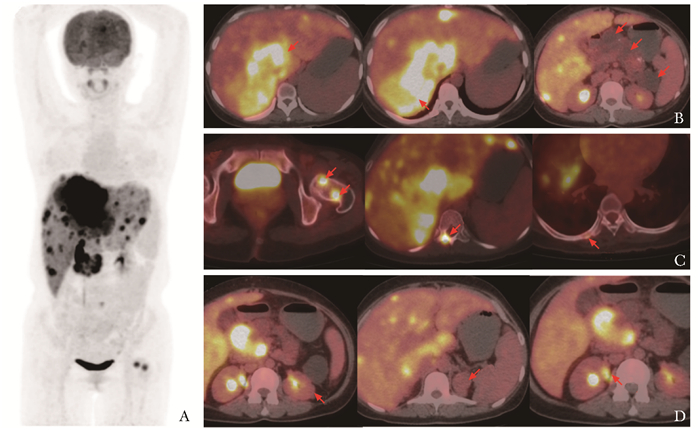

• 摘要: VHL(von Hippel-Lindau)综合征是一种罕见的常染色体显性遗传病。其临床表现复杂且多样,主要表现为视网膜、中枢神经系统、肾脏、胰腺等部位的多发肿瘤,患者常需进行全身多脏器评估。碳酸酐酶Ⅸ在VHL相关病变中普遍表达,68Ga-NY104作为一种新型小分子示踪剂,可对碳酸酐酶Ⅸ阳性病灶进行全身成像。本文报道一例32岁女性VHL综合征患者,先后行18F-FDG PET/CT和68Ga-NY104 PET/CT评估病灶,结果发现后者在更多种类的病灶(包括肾脏、胰腺、肝转移病灶及小脑病灶)中存在摄取。本文就该患者相关病灶的评估过程展开讨论,以期为探索VHL综合征患者的“一站式”评估手段提供借鉴。

Abstract: VHL (von Hipple-Lindau) syndrome is a rare autosomal dominant genetic disease with complex and diverse clinical manifestations, which primarily presents as multiple tumors in the retina, central nervous system, kidneys, pancreas, and other areas. Patients often require comprehensive multi-organ assessment. Carbonic anhydrase Ⅸ (CAⅨ) is ubiquitously expressed in VHL-related lesions, and 68Ga-NY104, a novel small-molecule tracer, can perform whole-body imaging of CAⅨ-positive lesions. This case report introduces a 32-year-old female patient with VHL syndrome who underwent sequential 18F-FDG PET/CT and 68Ga-NY104 PET/CT for lesion assessment. Notably, 68Ga-NY104 PET/CT demonstrated uptake in a broader range of lesions (including renal, pancreatic, hepatic metastatic lesions and cerebellar lesions). This article discusses the process of evaluating the relevant lesions in this patient, with the aim of exploring a "one-stop" evaluation tool for patients with VHL syndrome.